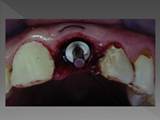

Implante de Incisivo central:

Implante de diente central: